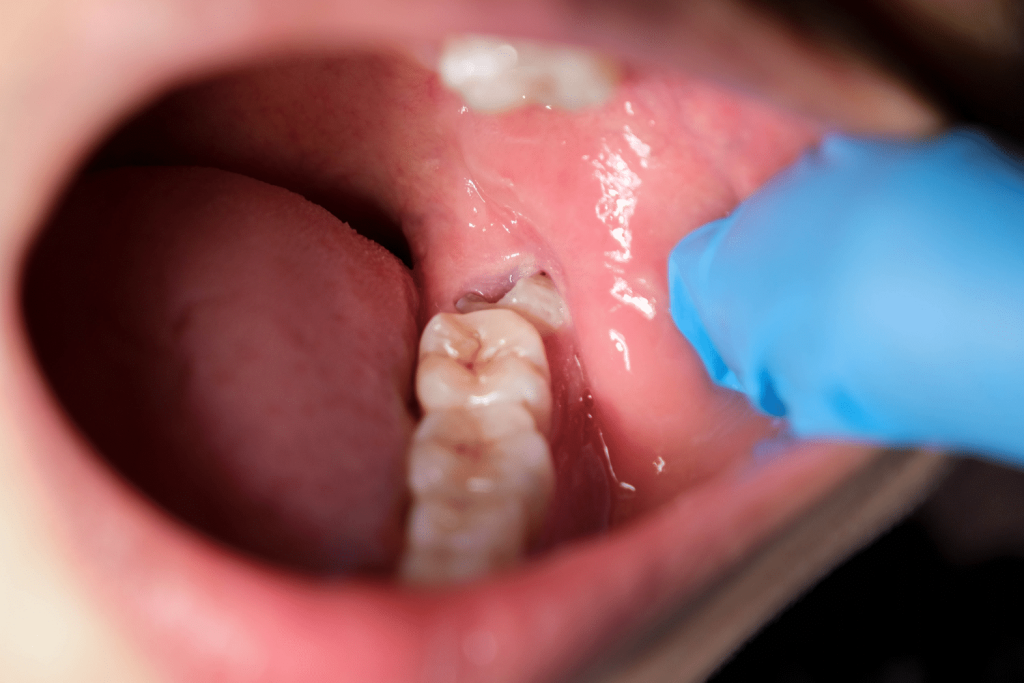

Maintaining strong, cavity-free teeth is essential for long-term oral health, especially for children and individuals more prone to decay. At Phoenixville Dental, we prioritize treatments that prevent dental issues before they begin, and one of the most effective preventive solutions is a fluoride sealant on teeth. Fluoride sealants provide a powerful layer of protection against […]